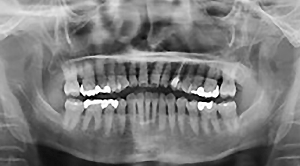

図❶ パノラマX線写真

画像所見:67にインレー処置が施行されているものの、根尖に透過像は認めなかった(図❶~❸)。